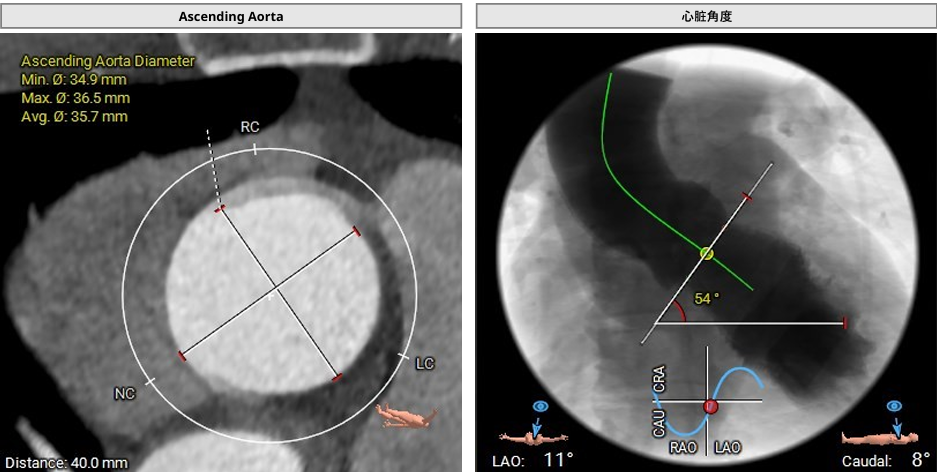

主动脉根部CT测量数据

心脏角度可,中度钙化

3. 主动脉弓呈锐角、心脏角度54°,右侧股动脉入路输送系统过弓和过瓣同轴性可。